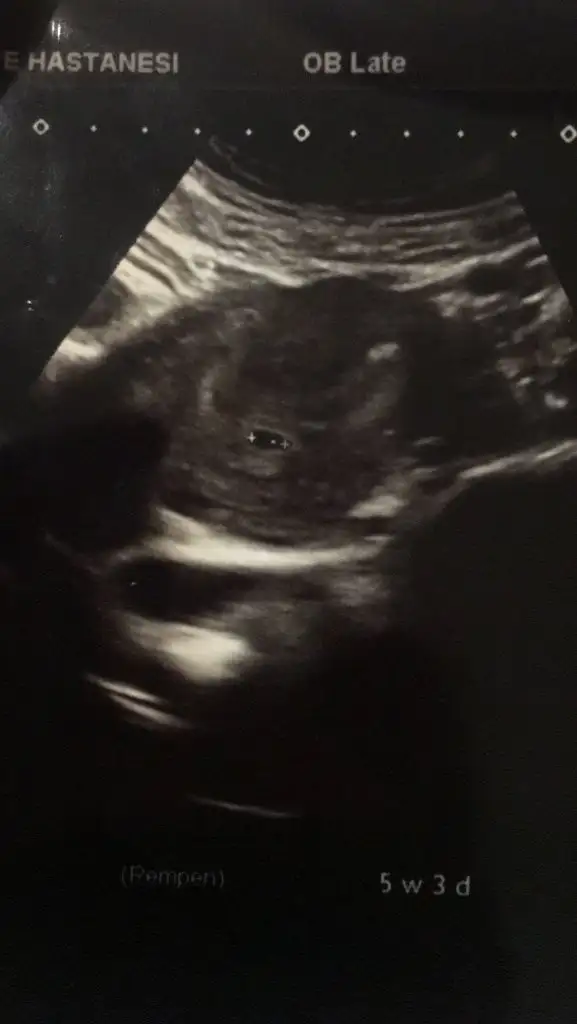

Ay ciddimisin bi yaşıma daha girdim şuna bi bakabilirmisiniz ilk çocuğumun resimleri cinsiyetini bilirse 2. Çocuğumun cinsiyetini daha erken öğrenebileceğim, çok heyecanlandım şimdidenKızlar bı arkadaş keseye göre tahmin yapıyor ve hep tutuyormuş iki oğlunu da bu şekilde cok yeniyken bile tahmin etmiş...ogullarinda kesesi hep uzunmuş muz gibi...yuvarlak ve yuvarlağa yakın olanlar hep kızdır diyor..ve bayağı emin konusuyor..benimki şişman bı fasulye gibi oo kesin kız görürsün dedi...sizlerin keselerinin şekli nasıldı ve cinsiyet neydi konusalimmi

Kesenin ucu mu yuvarlak ya da uzun olacak. 5 haftalık benim bebeğim kesenin ucunda muz gibi bir uzantı varKızlar bı arkadaş keseye göre tahmin yapıyor ve hep tutuyormuş iki oğlunu da bu şekilde cok yeniyken bile tahmin etmiş...ogullarinda kesesi hep uzunmuş muz gibi...yuvarlak ve yuvarlağa yakın olanlar hep kızdır diyor..ve bayağı emin konusuyor..benimki şişman bı fasulye gibi oo kesin kız görürsün dedi...sizlerin keselerinin şekli nasıldı ve cinsiyet neydi konusalimmi